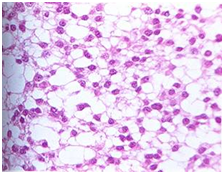

根据肿瘤的组织学特点,星形细胞瘤可分为纤维型、原浆型、肥胖细胞型等类型。下面是在显微镜下的常见的星形细胞瘤分型。

纤维性星形细胞瘤 原浆性星形细胞瘤

肥胖性星形细胞瘤 间变性星形细胞瘤